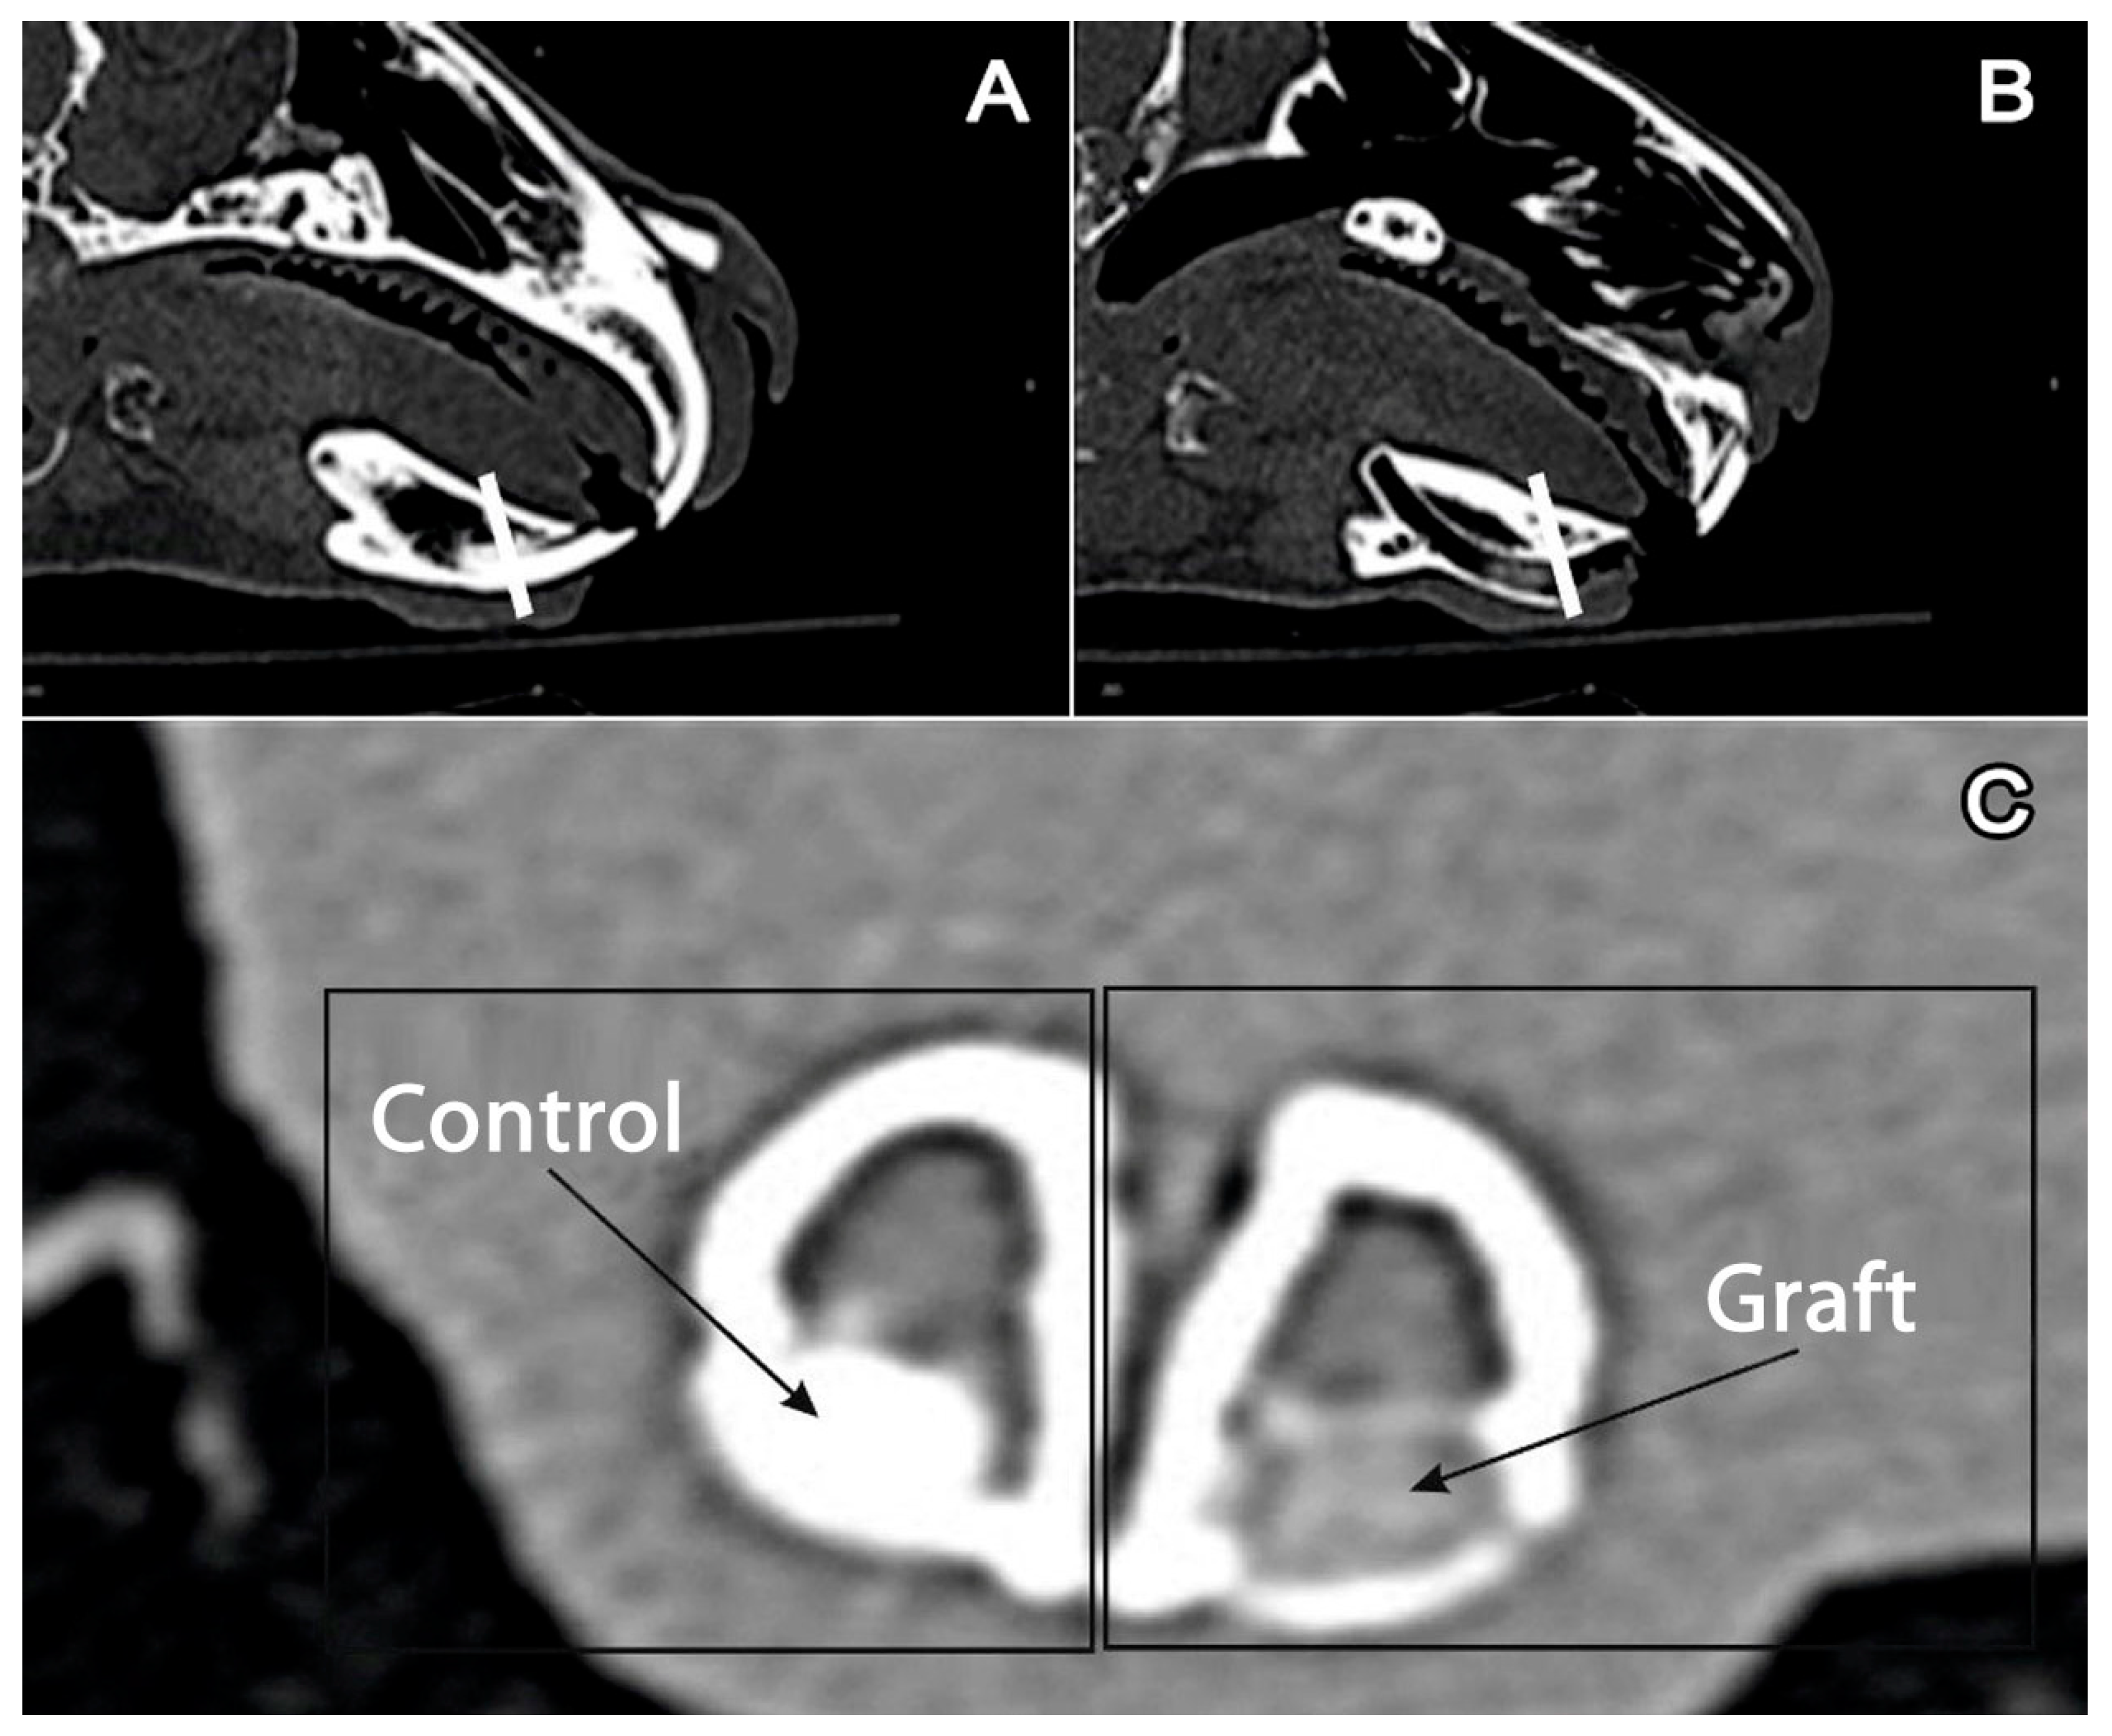

The authors studied the tissues that formed the alveolar ridge of the anterior section of the mandible. In the described anatomic area in the mandible of a rabbit, single-rooted teeth (incisors) are located. This anatomic area is shown in multilayer computed tomography (CT) images (Figure 1a–c).

Figure 1.

Multilayer computed tomography of the mandible: (A) intact side, a white line goes through the incisor. (B) The side with a removed incisor and graft in the alveolar fossa, a white line goes through the graft. (C) Cross-section of the mandible. Left: preserved incisor (control); right (graft): graft in the alveolar fossa.